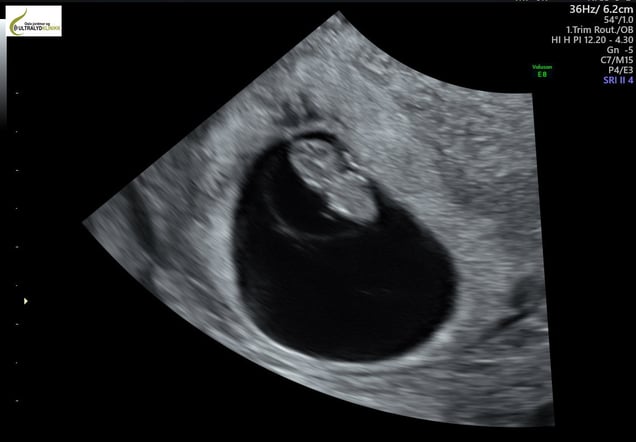

Ultralyd disse ukene gjøres vaginalt. Vi ser at fosteranlegget ligger på riktig plass i livmoren og at hjertet slår med en takt på rundt 130 -160 slag per minutt. Vi kan se hvor mange fostre kvinnen bærer på og måle fosteranlegget (CRL = Crown-Rump Length), og slik beregne hvor mange uker gravid kvinnen er.

Så tidlig kalles fosteranlegget for et embryo. (Den embryonale periode starter i uke 4 og ender i uke 10.) Embryoets mål disse ukene er 4 – 15 mm. Mot slutten av uke 7 vokser det frem små knopper som skal bli til armer og bein. Armene utvikler seg raskere enn beina.